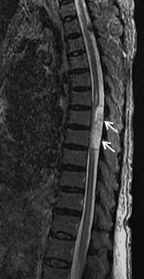

術前MRIでは多椎間で脊髄(灰色)を圧迫しています。後方手術施行後、脊髄への圧迫は改善しています。